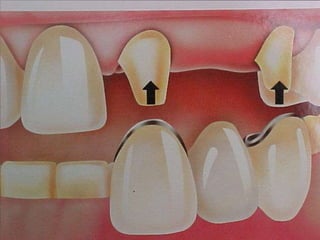

Las fuerzas de desalojo  en una restauración simple actuarán en dirección vestíbulolingualLas fuerzas de desalojo sobre un P.P.Fija tienden a actuar  con una dirección mesiodistalv.s.Debido a las fuerzas aplicadas a los dientes pilares a través del póntico, las fuerzas sobre los colados que sirven como retenedores para P.P.F.  son diferentes en magnitud y dirección de las que se aplican a restauraciones simples

Las fuerzas dedesalojo en una restauración simple actuarán en dirección vestíbulolingualLas fuerzas de desalojo sobre un P.P.Fija tienden a actuar con una dirección mesiodistalv.s.Debido a las fuerzas aplicadas a los dientes pilares a través del póntico, las fuerzas sobre los colados que sirven como retenedores para P.P.F. son diferentes en magnitud y dirección de las que se aplican a restauraciones simples